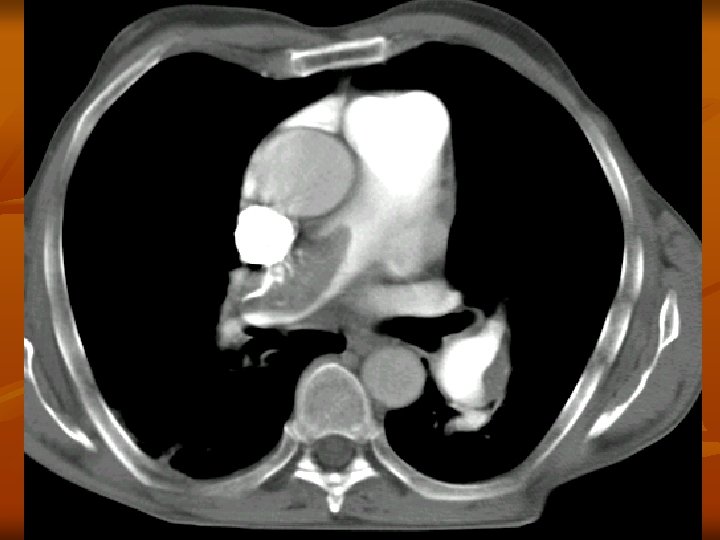

A CTA leggyakoribb alkalmazása dissectio esetén a CTA pontos választ ad: - dissectio fennáll vagy nem a dissectio kiterjedése, típusa kettős lumen megléte pericardium érintettsége supraaorticus ágak érintettsége visceralis ágak érintettsége ruptura occlusio esetén a CTA pontos választ ad az elzáródás helyére, collateralis keringés kialakulására, a parenchyma károsodására

A CTA leggyakoribb alkalmazása n n n Renovascularis és cerebralis vasculatura obliterativ folyamatának meghatározása Abdominalis és thoracalis daganatok műtéti eltávolítása előtt vasculatura ábrázolása Pulmonalis embolia gyanújának esetén! Első vizsgálati lépésként!